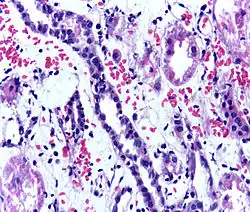

- Postoperative bleeding following kidney transplant as seen on ultrasound[88]

Postoperative bleeding following kidney transplant as seen on ultrasound[88]